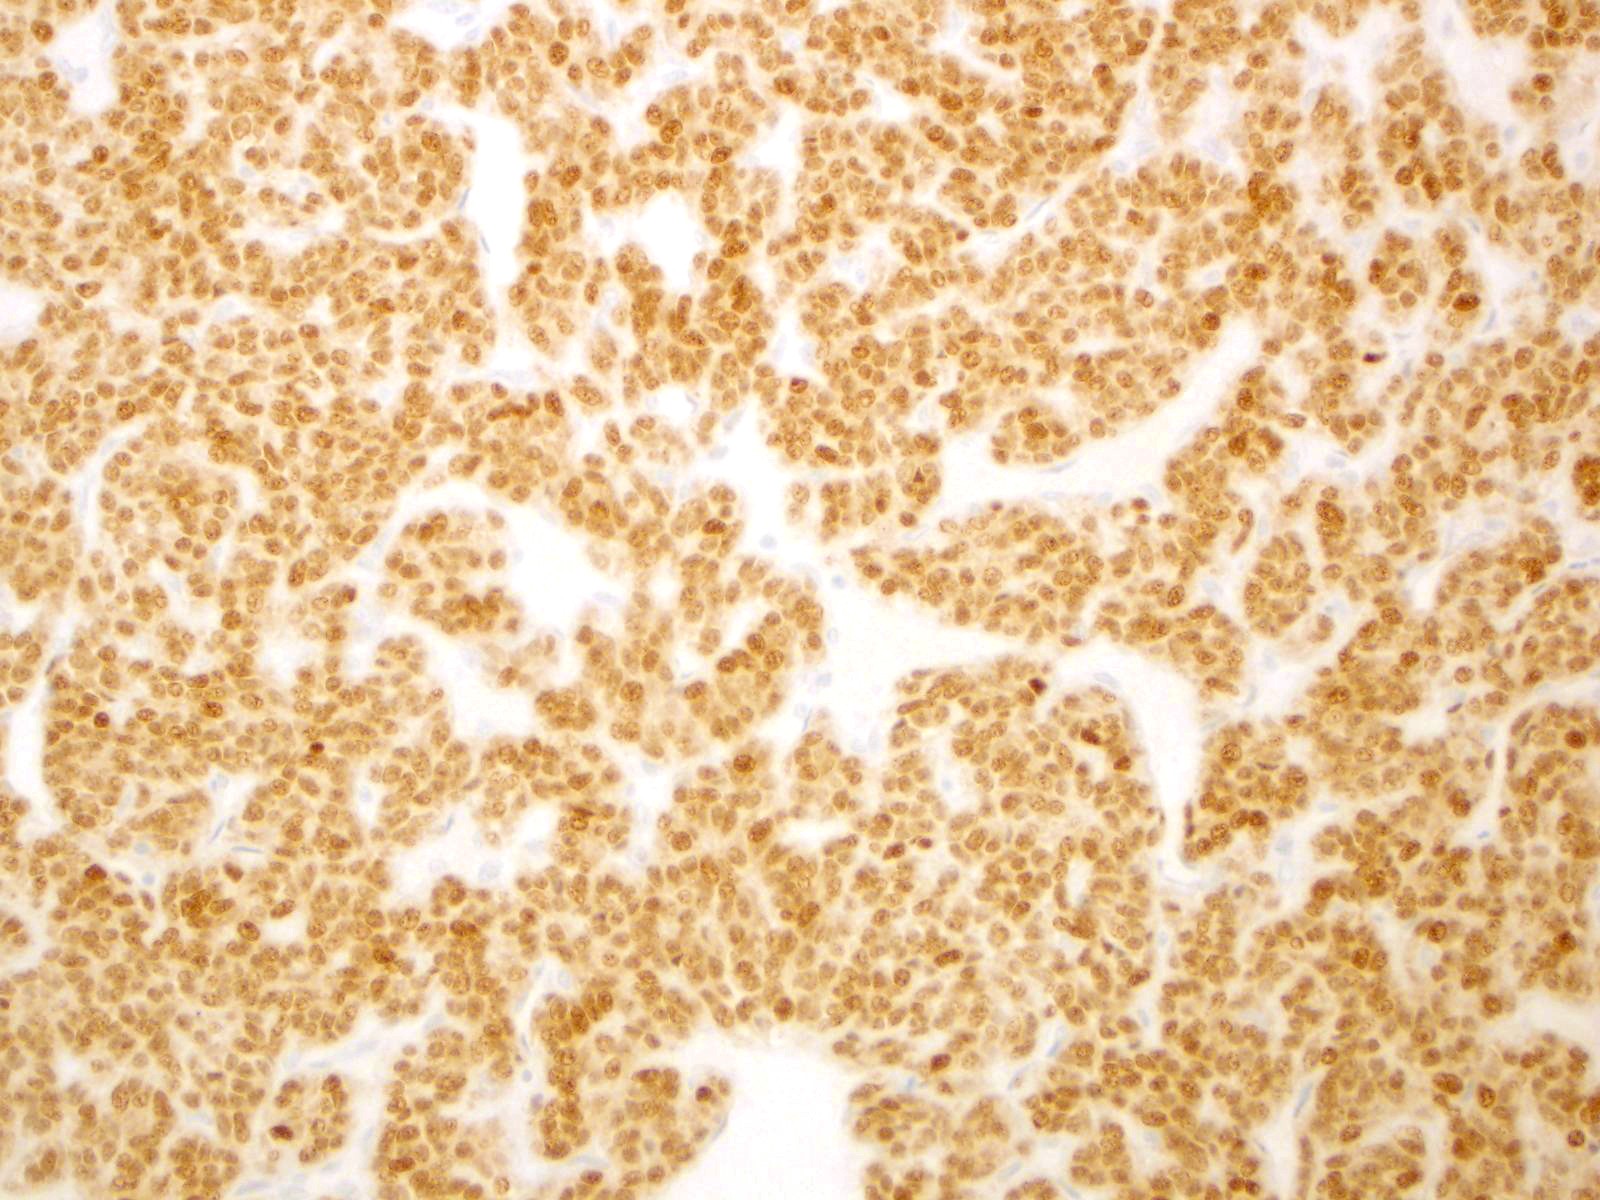

| 2SC |

S-(2-succino)-cysteine |

Hereditary leiomyomatosis and renal cell carcinoma (HLRCC) syndrome-associated RCC and leiomyoma

Most renal tumors and leiomyomas not associated with HLRCC

Staining Pattern

Cytoplasmic and nuclear

| HLRCC-associated RCC |

| Non-HLRCC-associated RCC |